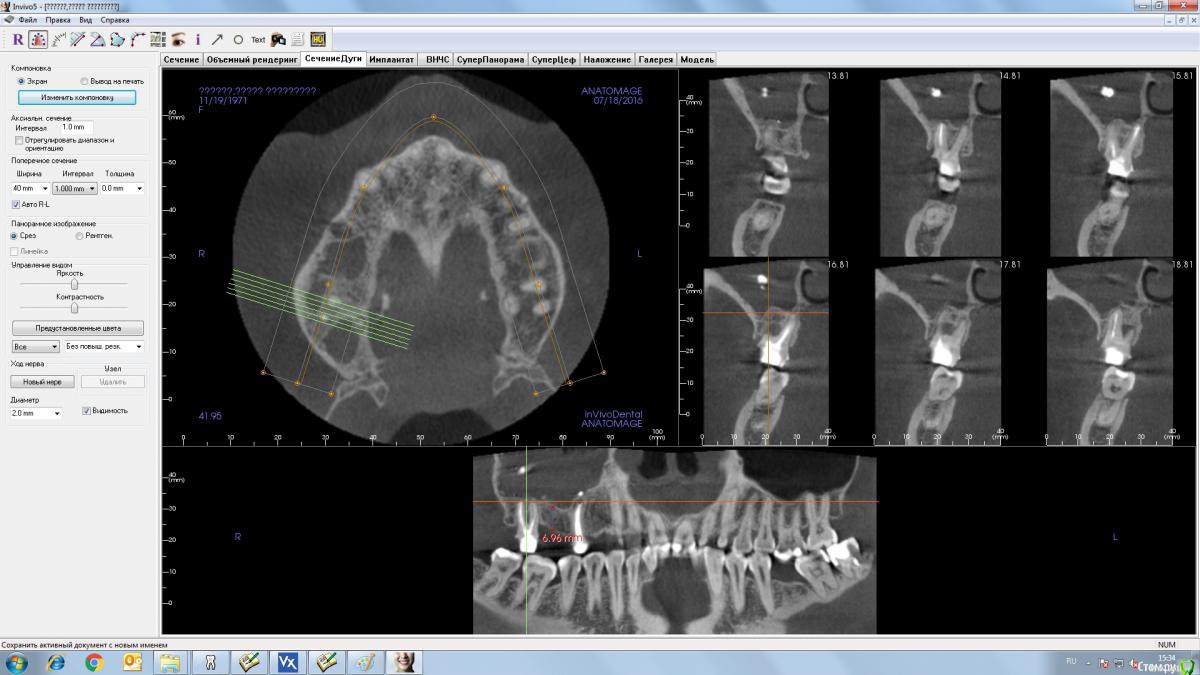

Andrey Shiryaev Опубликовано 19 июля, 2016 Автор Поделиться Опубликовано 19 июля, 2016 14 залезет без пробелем, а вот 16 там около 7 мм, т.е. Как минимум закрытый сделать нужно будет. Ссылка на комментарий

stommm Опубликовано 19 июля, 2016 Поделиться Опубликовано 19 июля, 2016 Можно поставить 6 мм имплант (если такие есть в системах которыми пользуетесь). С учетом того что потом будет 17 в связке, все ок Ссылка на комментарий

stommm Опубликовано 19 июля, 2016 Поделиться Опубликовано 19 июля, 2016 (изменено) Имхо если все равно зубы на удаление, то удалить, и сразу к лору. Материал из пазухи никуда сам не денется. А зубы могу стать причиной повторного инфицирования пазухи.У астры 4х6 есть, так что все отлично. После интеграции (или раньше если торк высокий) сделаете времяшки. А после 17 постоянные. Пациенту быстрее восстановите жевательную функцию и на 1 закрытый синус меньше. Вам можно быстрее начать имплантировать (даже сразу с удалениями совместить можно). И все довольны) Изменено 19 июля, 2016 пользователем stommm Ссылка на комментарий

Andrey Shiryaev Опубликовано 19 июля, 2016 Автор Поделиться Опубликовано 19 июля, 2016 Если во время удаления сделать имплантацию 4.0*6 в обл 16, 4.0*11 в обл 14, с формирователями, удаленные зубы ушить. стоит ли сделать подсадку в обл-ти 17, да бы не потерять кость? Далее отправляю к ЛОРу, и после него месяцев через 6 делаю имплантацию в обл. 17 по возможности в пределах кости? Ссылка на комментарий